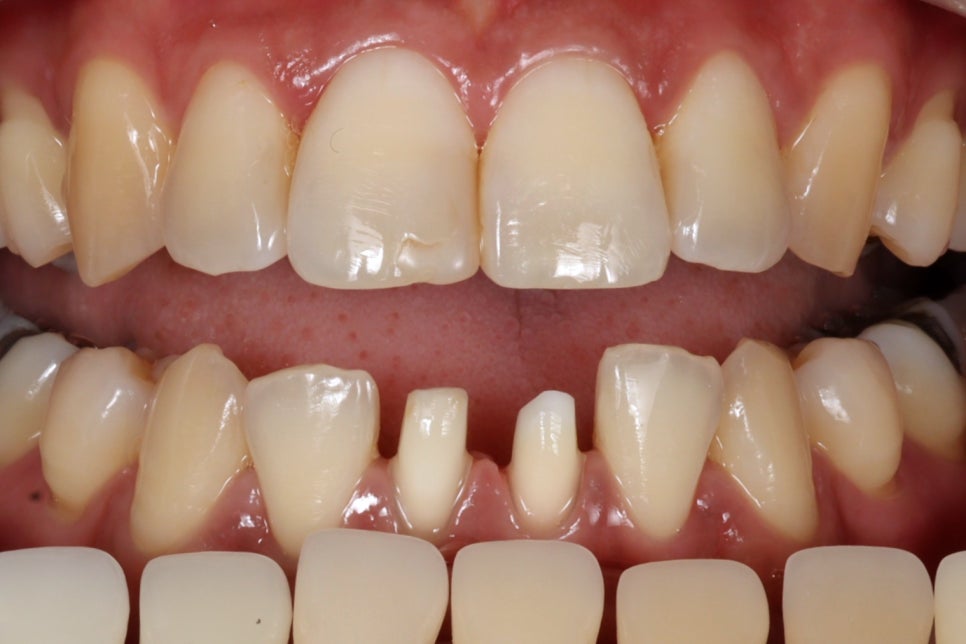

치료 완료

짜잔~

이번에도 저희 기공소장님께서

정말 말도안되게 자연스러운

지르코니아 크라운을 제작해주셨어요.

티도 안나고, 자연스럽습니다.

신경치료는 참

환자분들도 싫어하시지만

저희도 고충이 참 많은 치료입니다.

잘하기는 정말 어렵고

잘했다고해서 티도 안나죠..ㅋㅋ